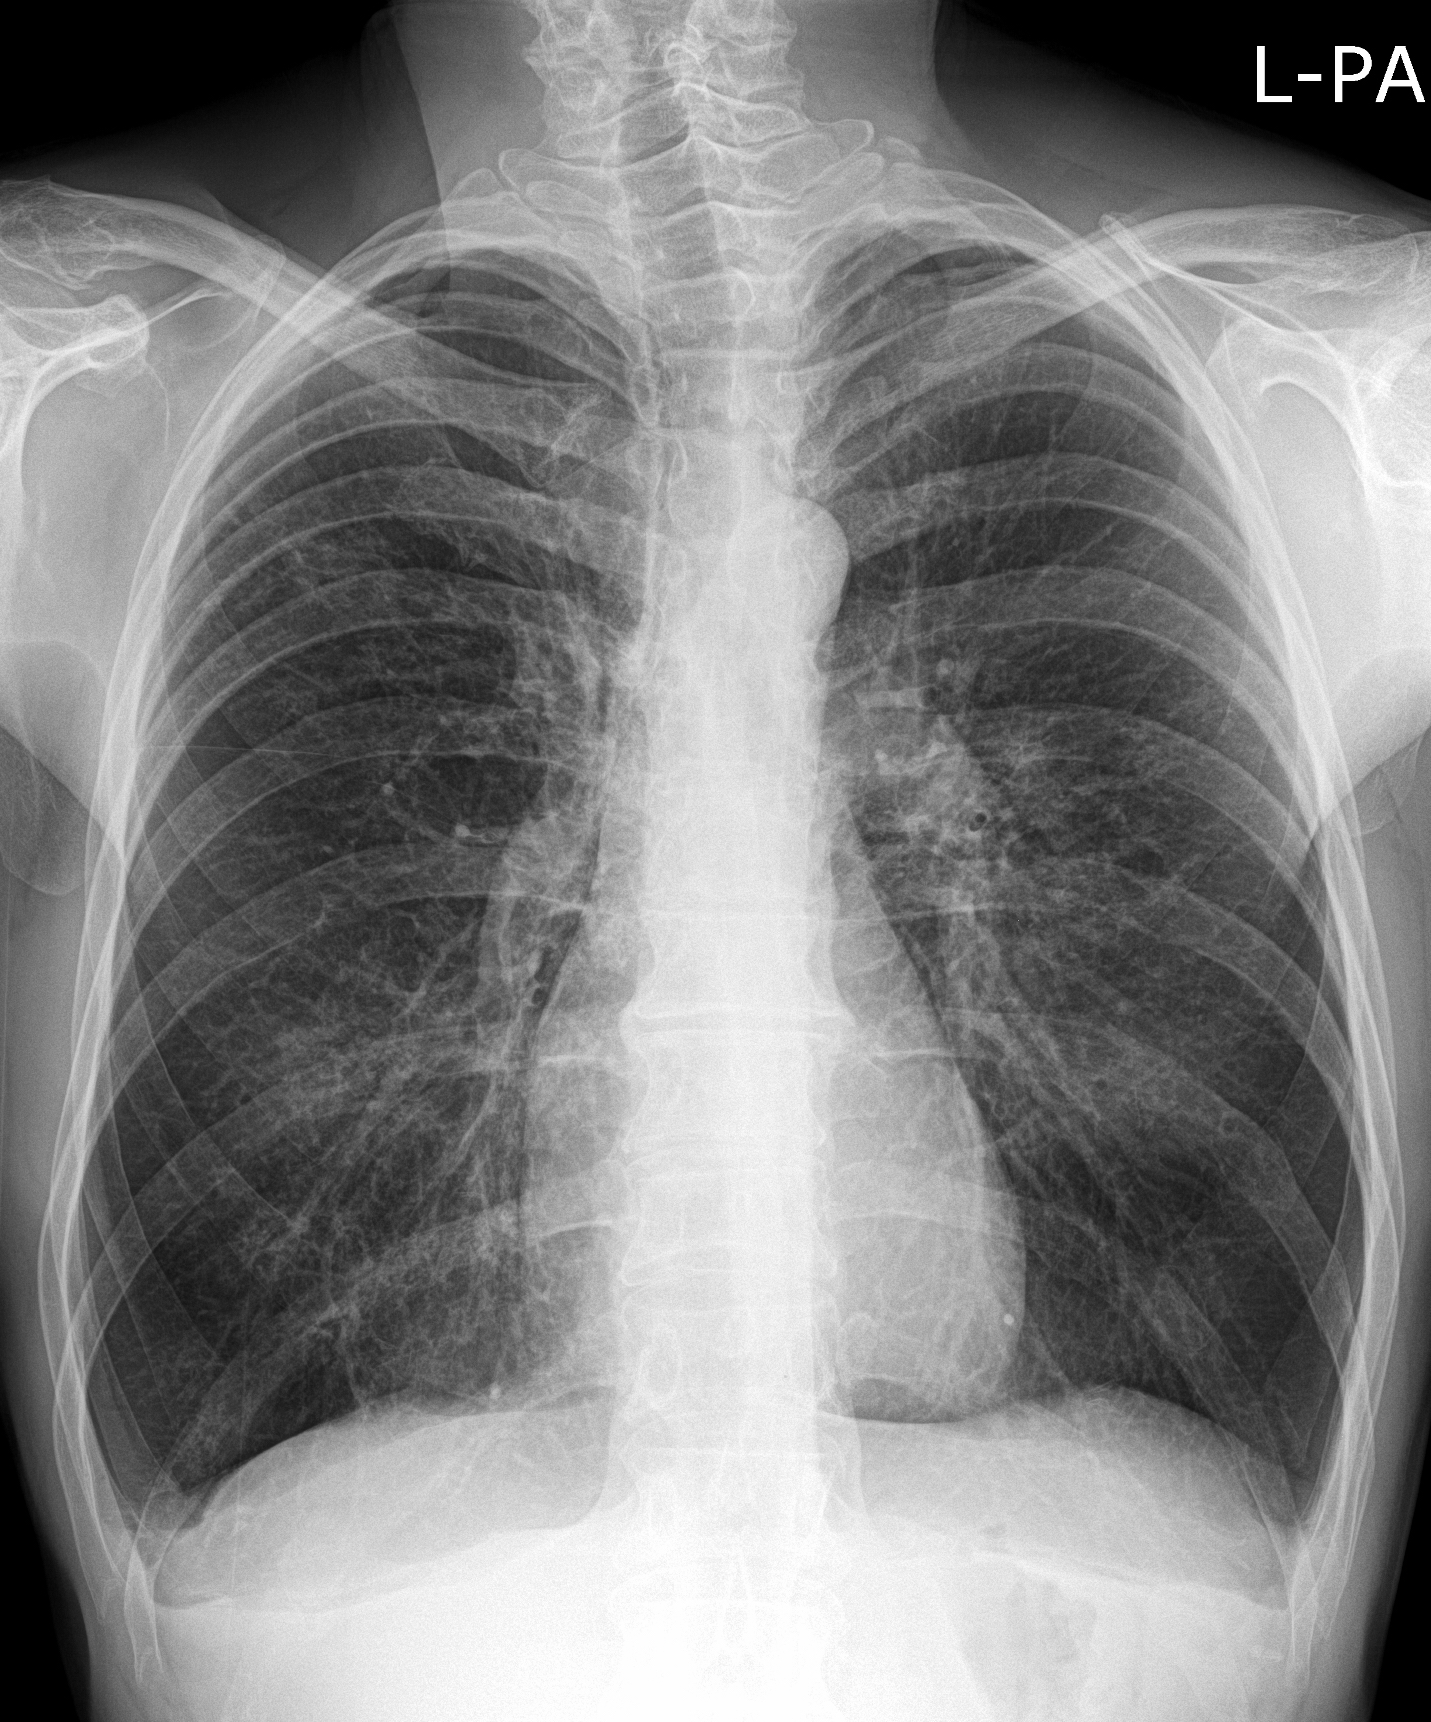

23. Pulmonary metastases, bidirectional (PA and right lateral) plain chest radiograph.

51 year old woman, endometrial carcinoma. Numerous ring shadows bilaterally in basal dominance (max. appr. 12 mm). Left pleural effusion of one finger wide.